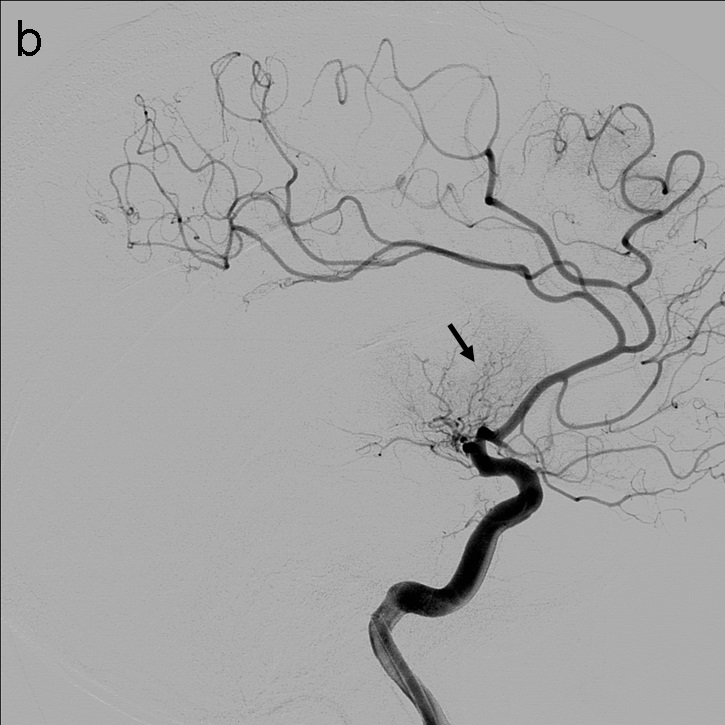

Tras la punción femoral derecha se asciende catéter balón FlowGate2 asistido por el catéter guía de asistencia punta Berenstein con guía de Terumo 0.035’’ para la cateterización de la arteria carótida común derecha y realización de estudio diagnóstico. Se obtienen series angiográficas en proyecciones anteroposterior y lateral de craneo que demuestran la presencia de trombo en el segmento M1 proximal de la ACM derecha (imagen 1). A continuación, mediante roadmap, cateterizamos la ACI derecha y realizamos un primer pase de trombectomía usando la técnica ADAPT a través del FlowGate2 con el AXS Catalyst 5 como catéter de aspiración, Trevo Pro 18 como microcatéter y con la microguía Asahi Chikai 0.014’’.